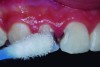

For the stepwise excavation, isolation with a rubber dam was performed prior to the removal of the infected tissue in the whole extension of the surrounding walls, with the aid of Nos. 3 and 4 rounded stainless steel burs at low speed. The disorganized dentin of the axial walls was removed with manual excavators (Figure 4). A 1-mm layer of calcium hydroxide paste was applied on the axial walls, and a GIC provisional restoration was performed; GIC was inserted with a syringe to avoid the incorporation of air bubbles into the material, thus, enabling better sealing. The option for a GIC relied on its good sealing properties, allowing more favorable conditions for the pulp-repairing activity.

Fig 4. Manual excavator removing tooth decay.

Figure 4